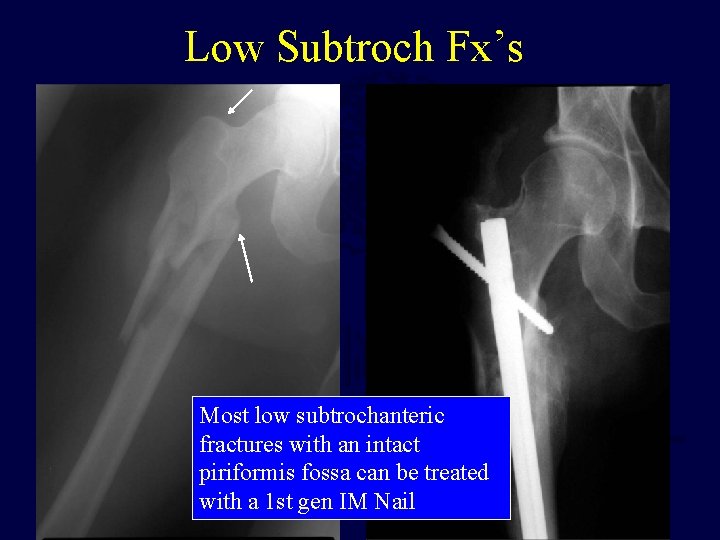

Low Subtroch Fx’s Most low subtrochanteric fractures with an intact piriformis fossa can be treated with a 1 st gen IM Nail